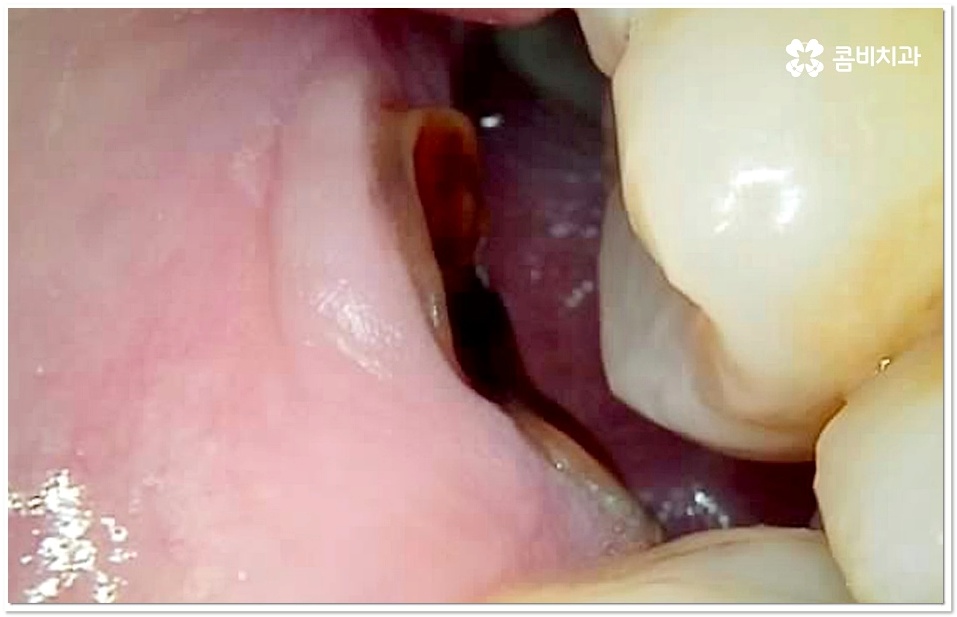

이 단계도 지나 치수까지 세균이 침투하게 되면 신경이 변성되고 통증이 심해지기 때문에 신경치료를 통해 이를 제거하고 내부에 충전재를 채워 밀봉한 뒤 전체를 덮어씌우는 크라운 치료를 해 주는데, 이와 같은 보존적 어금니 충치치료 로 자연 치아를 발치하지 않고 내구성을 좀 더 늘릴 수 있습니다.

강도가 중요한 어금니 크라운 재질로 예전에는 금을 많이 사용했었지만 요즘은 자연스러운 심미성을 추구하는 추세라서 치아 색상의 지르코니아를 많이 사용하고 있는데요.

어금니 충치치료 후 신경이 제거된 치아는 추후 2차 감염이 일어나더라도 개인차가 있으나 통증을 느낄 수 없는 경우가 있고, 뿌리쪽에 염증이 생기거나 크라운 안쪽에서 2차 충치가 발생된 경우 육안으로 발견하기도 어렵기 때문에 치료 시기가 더욱 늦어질 수 있어요. 이런 상황에 대비하여 정기적으로 치과에 내원하여 정밀 검진 및 스케일링 처치를 받아주시면 예방과 관리가 한결 용이할 거예요.